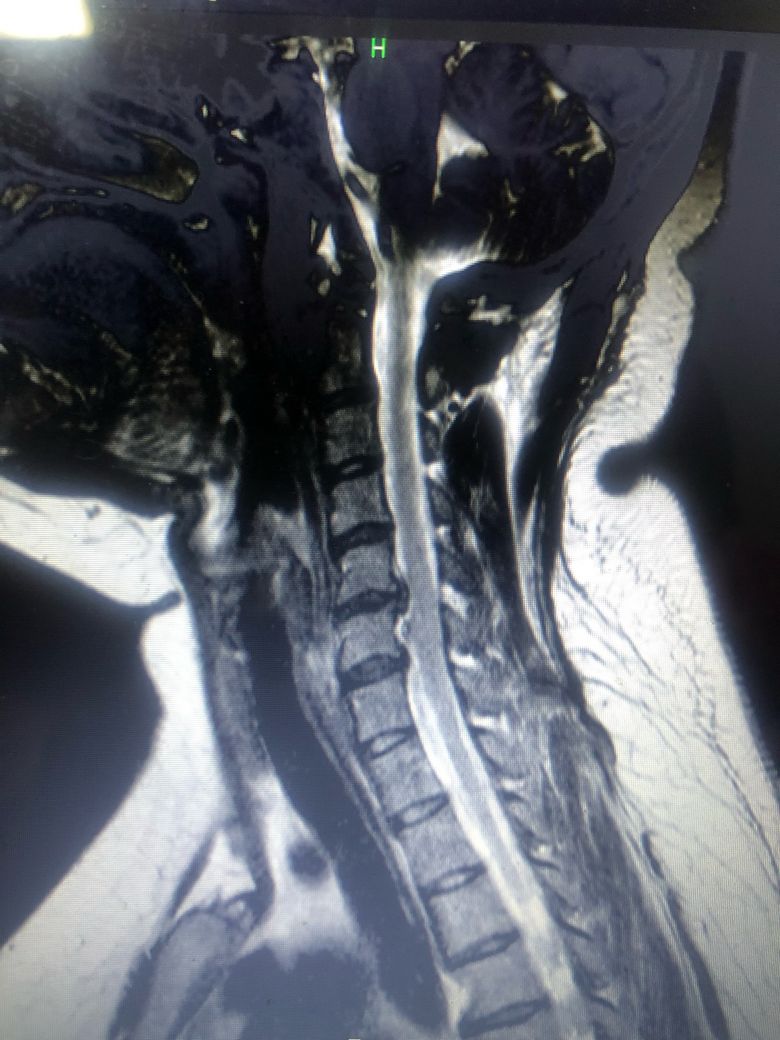

• 2번 째 사진